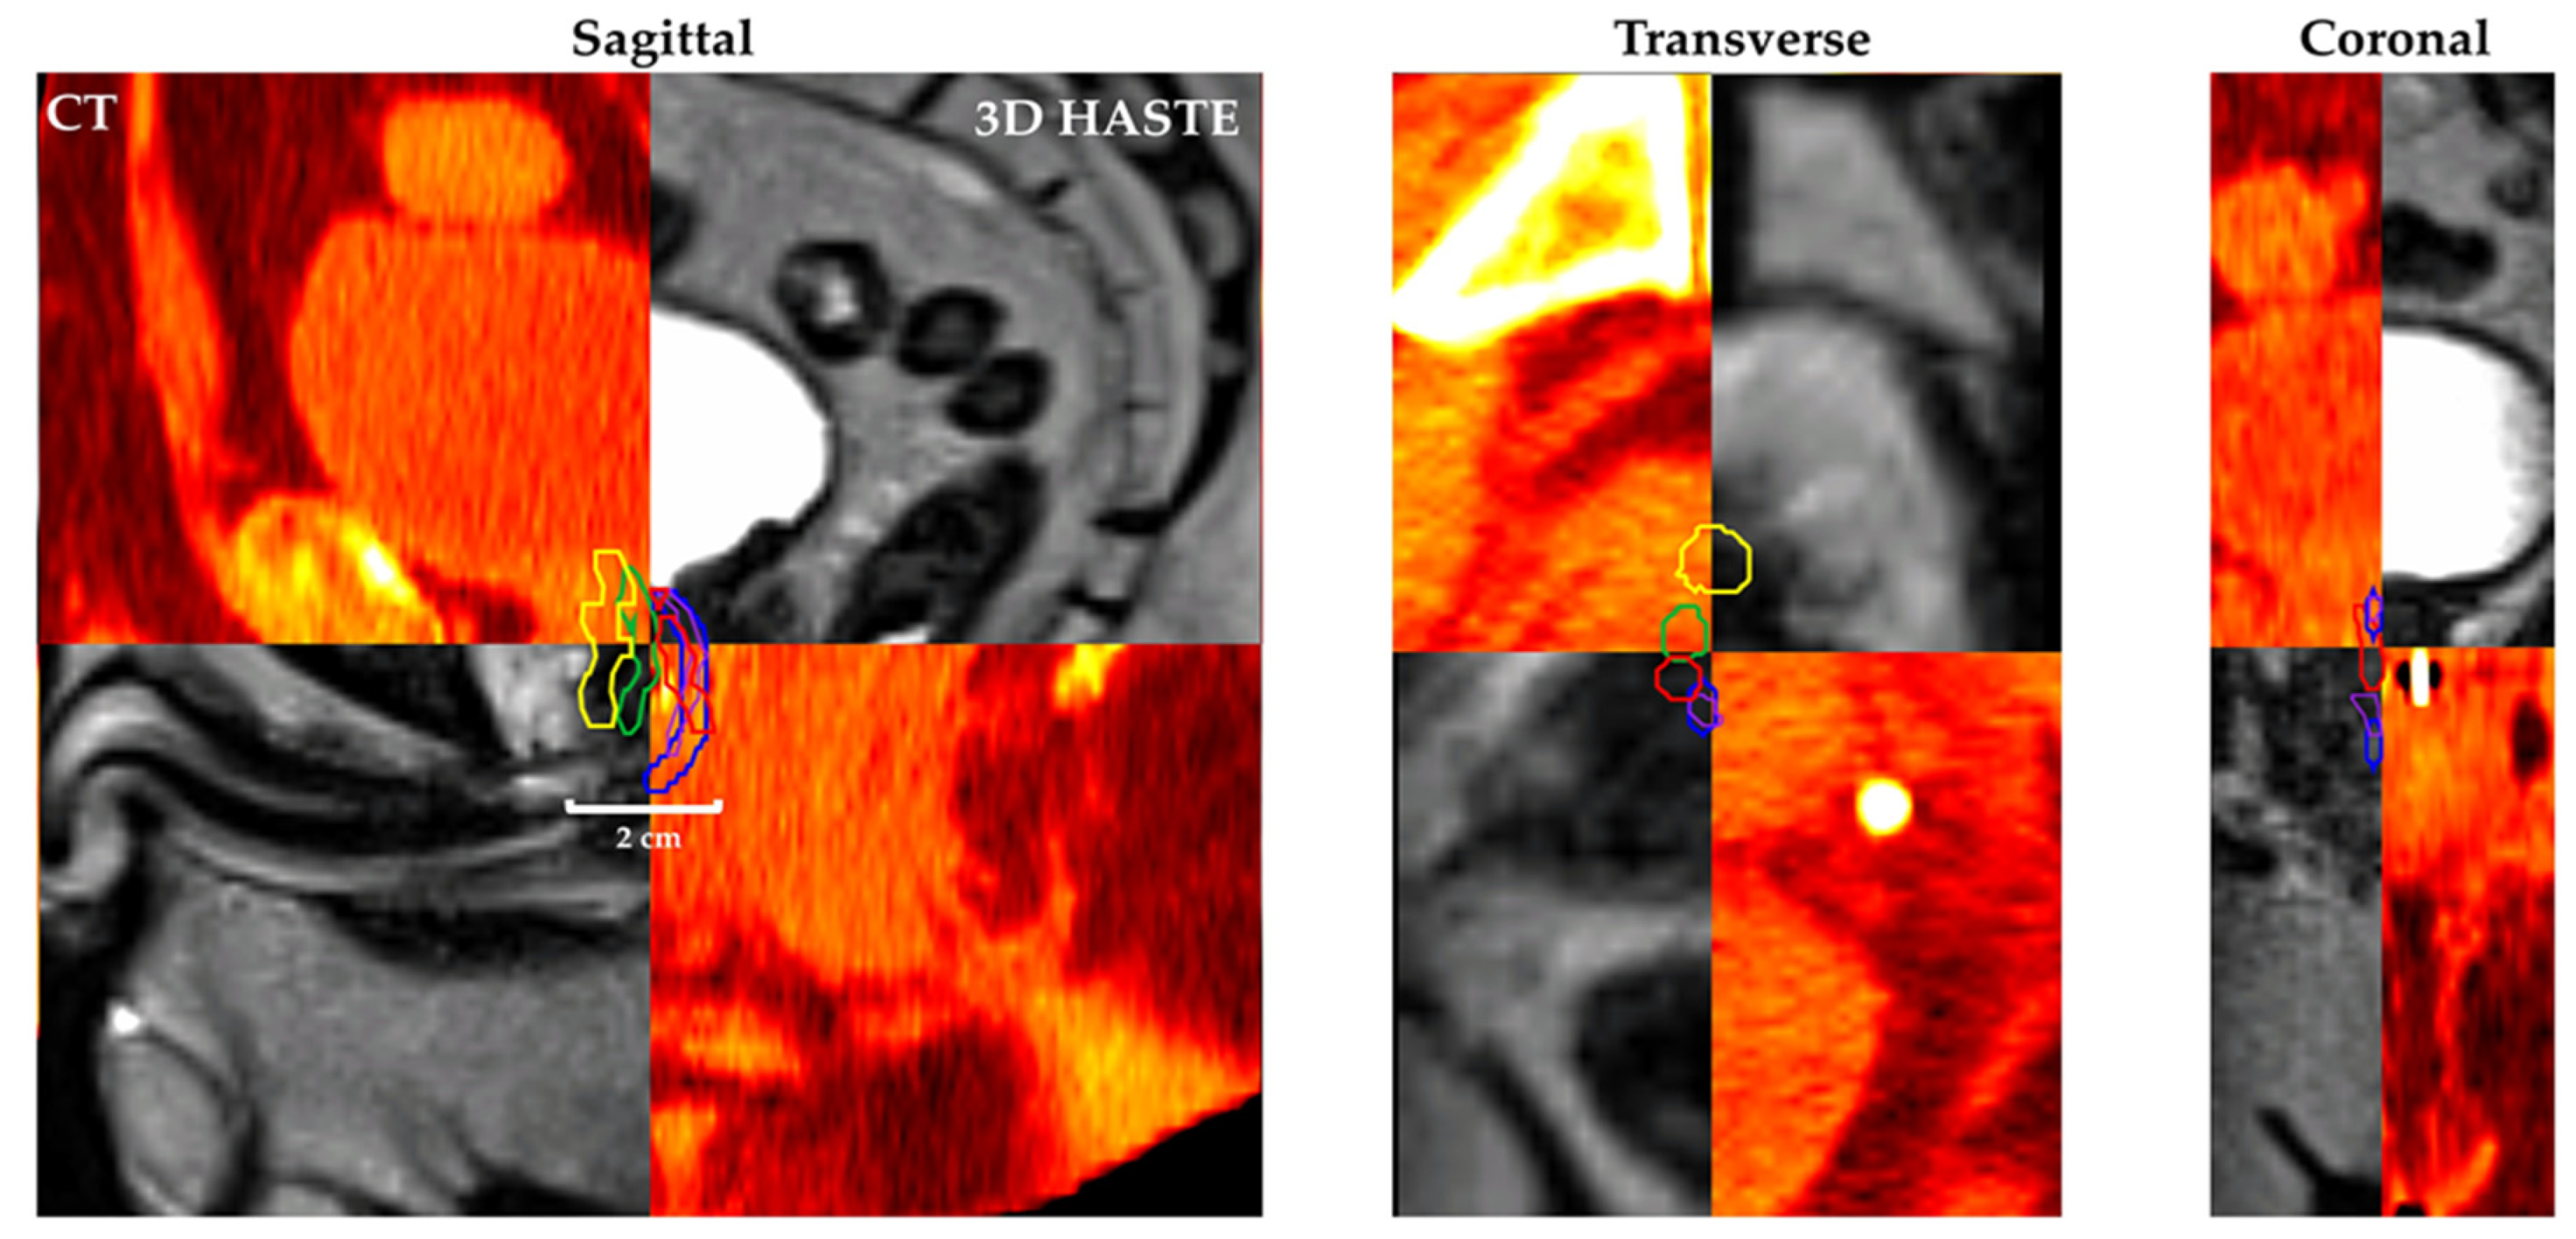

Figure 4 shows Patient 7’s CT and MRgRT 3D HASTE fused image with urethra contour based on CT-1: CT only (yellow), CT-2: CT + diagnostic T2w MRI (green), MRgRT-1: MRgRT 3D HASTE (red), MRgRT-2: MRgRT 3D TSE (blue), and MRgRT-3: clinical MRgRT 3D bSSFP (purple).

Figure 4. Patient 7’s CT (red/yellow) and MRgRT 3D HASTE (B–W linear) fused image with urethra contour based on workflow (1) CT-1: CT only (yellow), (2) CT-2: CT + diagnostic T2w MRI (green), (3) MRgRT-1: MRgRT 3D HASTE (red), (4) MRgRT-2: MRgRT 3D TSE (blue), and (5) MRgRT-3: clinical MRgRT 3D bSSFP (purple) prostatic urethra contour.